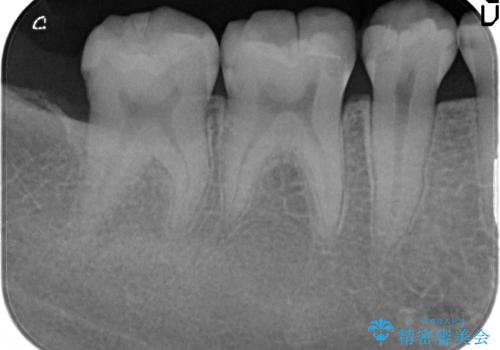

X線撮影を行った結果、詰めた箇所の下部に虫歯の再発を認めました。

再発した虫歯は神経に近いことが多く、丁寧に除去することで神経を温存し、精密なセラミック修復を行うことで更なる虫歯の再発を防ぎます。

虫歯治療後の虫歯の再発は、神経の治療(根管治療)が必要になることも多くなってしまいます。